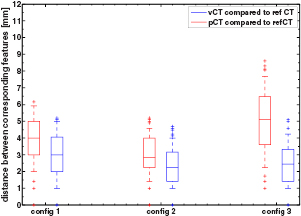

Figure 4 presents the results of the aSIFT evaluation for the 6 possible image inter-comparisons using Tz = 6 mm. We observed that the median distance between corresponding features was lowered when comparing the vCTCBCT, refCTCBCT and CBCTCBCT together, indicating that our registration algorithm yielded a vCTCBCT which agreed better with the CBCTCBCT/refCTCBCT than the pCTCBCT. The median distances are of the order of 2–3 mm, which is comparable to the planning CT resolution of 1.074 mm in the axial plane and 3 mm in the scan direction. Interpolating the CT to the CBCT coordinate system does not improve its resolution, however the fact that the phantom is homogenous in the Z direction means that for homogeneous parts of the phantom this interpolation should yield similar values as a higher resolution reconstruction. This is however not true at edges, where most features are detected. It is thus likely that our results are limited by a combination of the precision of the aSIFT algorithm and the slice thickness used. The median feature distances for the vCTCBCT versus refCTCBCT and pCTCBCT versus refCTCBCT comparisons are reported in table 3 before and after outlier removal. A Wilcoxon rank sum test between the feature distances of the vCTCBCT versus refCTCBCT and pCTCBCT versus refCTCBCT after outlier removal yielded p < 0.01. The aSIFT algorithm yielded matching features between the vCTCBCT and refCTCBCT/CBCTCBCT which exhibited large differences in their Z positions, hence the need for a Tz rejection. This is illustrated in figure 5 where accepted and rejected features are shown.

Figure 4. Boxplot of the distance between corresponding features for the 6 comparisons investigated after applying TZ = 6 mm. The horizontal line represents the median distance; the blue box represents the 25th and 75th percentiles and the whiskers extend to the most extreme data point not considered an outlier (plotted as red crosses). The median calculated here includes outliers, as opposed to table 3. Images were in the CBCT coordinate system.

Download figure:

Standard image High-resolution imageFigure 6 presents the results of the aSIFT evaluation between the pCTCBCT versus refCTCBCT and vCTCBCT versus refCTCBCT for all configurations. As expected configuration 3 shows the largest difference between pCTCBCT and vCTCBCT, however the vCTCBCT shows lower median feature distances than the pCTCBCT for configurations 1 and 2 as well.

Figure 6. Boxplot of the distance between corresponding features for the 3 configurations. The horizontal line represents the median distance; the blue box represents the 25th and 75th percentiles and the whiskers extend to the most extreme data point not considered an outlier (plotted as red crosses).

Download figure:

Standard image High-resolution imageFigure 7 presents profiles across the phantom comparing the vCTCBCT, refCTCBCT and pCTCBCT. We observed good geometrical agreement between vCTCBCT and refCTCBCT and no noticeable degradation of CT number accuracy was observed in uniform regions. A discrepancy between the vCTCBCT and the refCTCBCT can be observed in the range of 40–50 mm due to the deformation of the muscle insert in the vCTCBCT. A second discrepancy is observed between 110–120 mm due to the imperfect fit of the airway sleeve in the refCTCBCT which caused a narrow air gap. Table 4 presents the volumes of the automatically segmented inserts and their DICE coefficients between vCTCBCT/refCTCBCT and pCTCBCT/refCTCBCT. Good agreement was observed between the vCTCBCT and refCTCBCT, with DICE coefficients between 0.83 to 0.99, an improvement from pCTCBCT versus refCTCBCT. The worst performance in term of DICE coefficients was the muscle insert which was distorted by the deformation. The DICE coefficients for the vertebral column inserts from the pCTCBCT versus refCTCBCT comparison, which had constant volume, were below 0.9 due to the misalignment from the rigid registration between pCTCBCT and refCTCBCT which can be observed in figure 3. However the volumes of the vertebral column inserts were consistent across all scans. Insert volumes were lower than the nominal 35.3 cm3 due to imperfect insert segmentation. The errors on the volumes are consistent with an underestimation of the insert radius by 1 mm which is of the order of the CBCT voxel size. When considering configurations 1 and 2 similar results were obtained, however in those cases the volume of the muscle insert was preserved in the vCTCBCT.